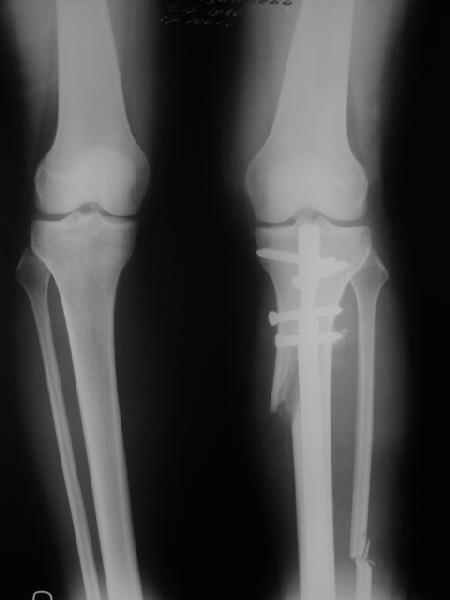

Снимки в приложении - фас сравнительный с неоперированной ногой. Жду критики.

It is very interesting to me that as you have derotated the tibia you have centred the patella, I think and the prox tibia looks much more anatomic.

The analysis in the attached images is direct, just using the tools.

Tibial tilt is perhaps more than you want but the tibial correction is to 90 (very slight over

correction.

Will need full length views to tell us about the hka but it appears neutral.